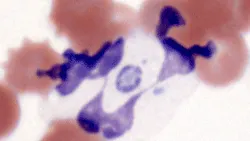

Case 3: Prior History of Leukemia & Chemotherapy

An 8-year-old, castrated male mixed-breed dog with a prior history of leukemia and chemotherapy was presented for a follow-up CBC. Table 1 provides blood analysis results; Figures 6 and 7 show the blood films.

Featured Image

Figure 6. In dogs, the predominant leukocyte is the neutrophil. However, in this case, large lymphoblasts predominate. Pale staining, oval nucleoli are visible in 2 of the lymphoblasts (lower left cell, lower right cell). Erythrocyte density is moderately reduced and numerous intraerythrocytic piroplasms are present. (Wright-Giemsa, 100×)

Figure 7. Figure 6 magnified to show intraerythrocytic piroplasms consistent with Babesia canis. Immunosuppressive chemotherapy likely unmasked a latent B canis infection, which caused parasitemia and contributed to this dog’s anemia. (Wright-Giemsa, 100×)

Diagnosis: Acute lymphocytic leukemia (no longer in remission) with Babesia canis infection unmasked by immunosuppressive chemotherapy

Interpretation & DiscussionAlthough the total leukocyte count was within the reference interval, evaluation of leukocyte morphology in the blood film revealed that abnormal leukocytes, specifically large lymphoblasts, were the predominant cell type (Table 3). Once the blasts were included in the manual leukocyte differential as a separate category, the absolute counts of the other leukocyte types decreased.

Erythrocyte morphology was also abnormal. There were numerous intraerythrocytic piroplasms consistent with Babesia canis, which cannot be detected by hematology analyzers (Figure 13). In this case, the blood film contained important additional information that only a trained microscopist could discern during evaluation.

Did you answer…

• The patient is out of remission since the predominant nucleated cell is the lymphoblast.

• The automated leukocyte differential is not accurate since the blast cells were not reported by the analyzer.

• The intraerythrocytic inclusions are presumably Babesia canis.

Figure 13: Figure 6 magnified to show intraerythrocytic piroplasms consistent with Babesia canis and a lymphoblast with a pale staining, oval nucleolus at the nuclear margin (right).